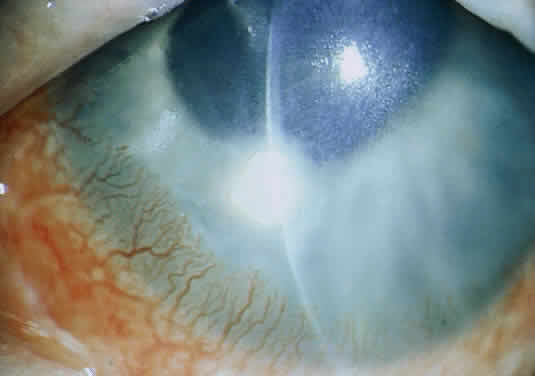

The more peripheral marginal infiltrate is sterile and is caused by a hypersensitivity reaction to the exotoxin or the bacterial antigens of S. aureus.35,36 The peripheral infiltrates usually are associated with blepharitis or conjunctivitis and frequently begin in the areas where the lid margins cross the limbus (at 2-, 4-, 8-, and 10-o'clock positions). The lesions often have a typical clinical appearance characterized by one or more small, well-circumscribed anterior stromal infiltrates, with a lucid interval between them and the limbus (Fig. 3). Although the epithelium is usually intact, it may break down, leading to ulceration, scarring, and neovascularization.